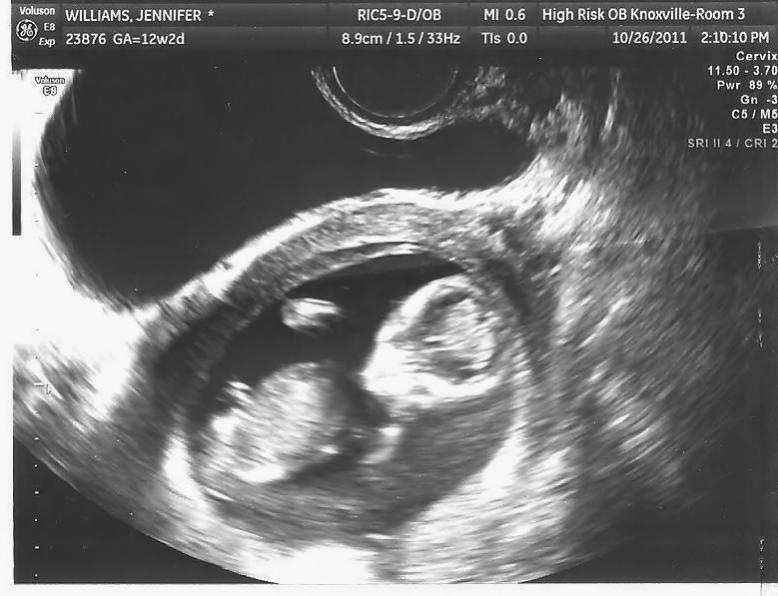

We need a profile pic where you can see the spine. Sorry:( do you have any other pics?

no its the only one i have